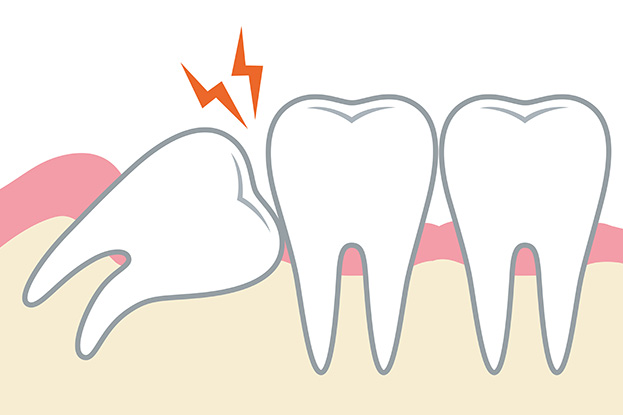

「親知らず」は、顎(あご)の一番奥に生える歯で、永久歯のなかで最後に発育します。正式には第3大臼歯(だいさんだいきゅうし)といいますが、成人になって知恵がついて生えることから「智歯(ちし)」とも呼ばれています。また、親の手を離れ、親の知らぬ間に生えてくることが名前の由来といわれています。

「親知らず」には個人差があります。はじめからない方や上下左右の4本が揃っていない方、また、まっすぐに生えてくるとは限らず、横や斜めに生えたり、埋まったままだったりします。他の歯と同じように正常に生え、しっかりかみ合っている場合はとくに問題はありませんが、悪影響をもたらすような生え方の場合は、抜歯を検討する必要があります。

「親知らず」のトラブルは顎の大きさと関係性があります。現代人の顎の骨は昔と比べ小さくなってきていますが、歯の大きさはあまり変わっていません。そのため、一番最後に生えてくる「親知らず」は、スペースが足りず、正常に生えてこない場合が多いのです。斜めに生えてきたり、一部分だけ頭を出していたり、顎の中で水平で埋まったままということもあります。こうした状態にあると、むし歯や炎症を起こしたり、歯並びの悪化や顎関節症の原因になったりすることもあります。

「親知らず」の痛みは、生えてくるときに歯肉が他の歯によって傷つけられたり、細菌に感染し炎症を起こしたりすることによって生じます。